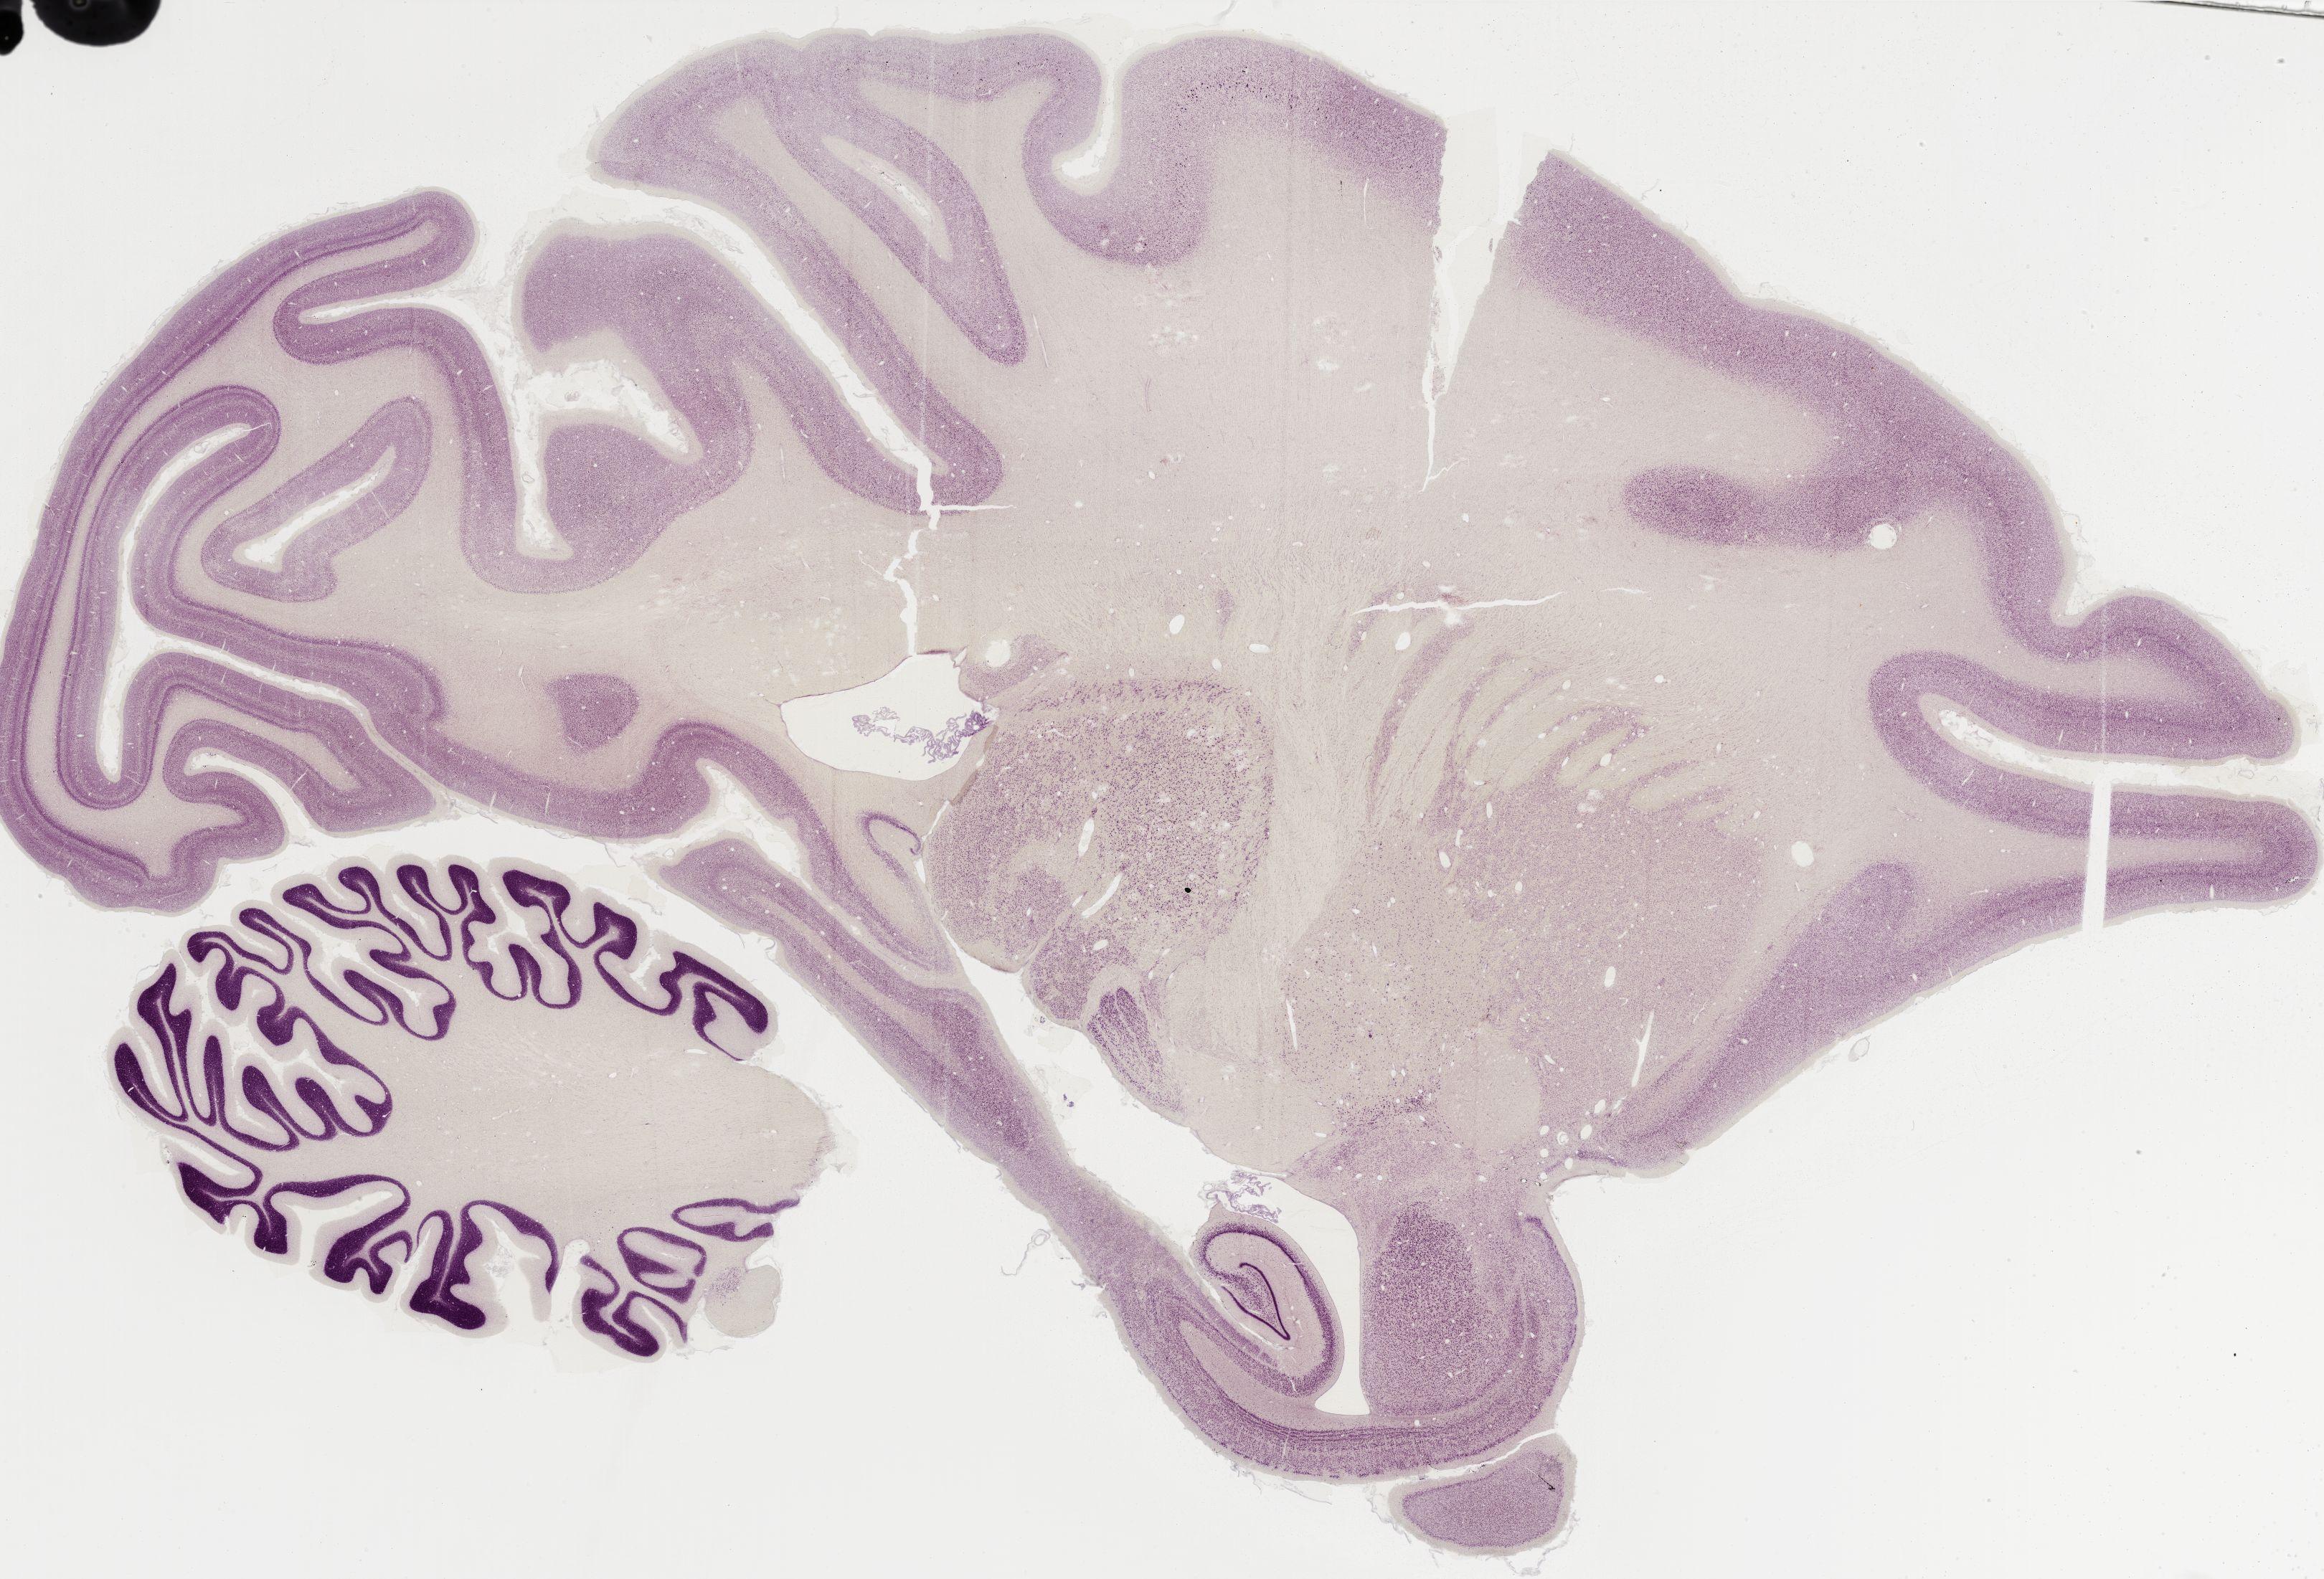

Datasets -> Macaca Mulatta -> Nissl, sagittal, histo, Whole-Brain, adult

[ Metadata ]   ·   Source: Edward G. Jones

Displaying Sections 161 thru 200 of 295 Sections for this Dataset

0367 - labeled